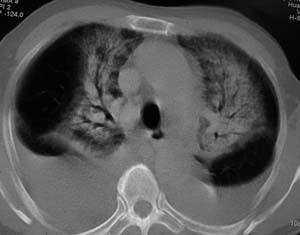

以下是引用zyx168在2007-1-21 17:08:00的发言:[br]男,71岁,咳嗽、胸闷10天余,咯血1天。[br]两肺大片状密度均匀影,充气支气管征象明显,左房增大,双侧胸腔内新月形液性密度影。[br]考虑:1,心源性肺水肿伴双侧胸腔中等量积液;[br] 2,两肺肺炎?